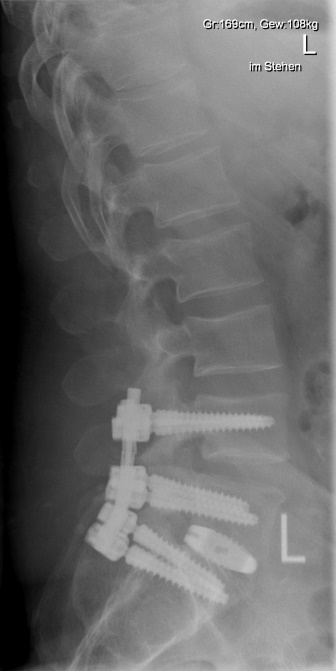

Beim Wirbelgleiten (Spondylolisthese) verschieben sich einzelne Wirbelkörper zueinander. Dies kann durch Abnutzung oder angeborene Verknöcherungsstörungen bedingt sein und sowohl in hohem Alter als auch in der Jugend zu Beschwerden führen. Das Wirbelgleiten kann durch die damit verbundene Instabilität zu Rückenschmerzen oder auch durch Verengungen an Wirbelkanal und Nervenaustrittslöchern zu schmerzhafter Ausstrahlung in die Beine führen. Sollten krankengymnastische Behandlungen oder minimalinvasive Therapiemöglichkeiten, keine Beschwerdelinderung erreichen, so wird in einer Operation zunächst das regelrechte Profil der Wirbelsäule wieder hergestellt und anschließend stabilisiert (Repositionsspondylodese). Die zwischen den Wirbelkörpern liegende Bandscheibe ist in der Regel zerstört und wird durch einen Platzhalter ersetzt. Diese Maßnahme kann von vorne, von der Seite oder von hinten am Wirbelkanal vorbei durchgeführt werden, sie ist wesentlich zur Festigung der Versteifung.

Beispiel Wirbelgleiten